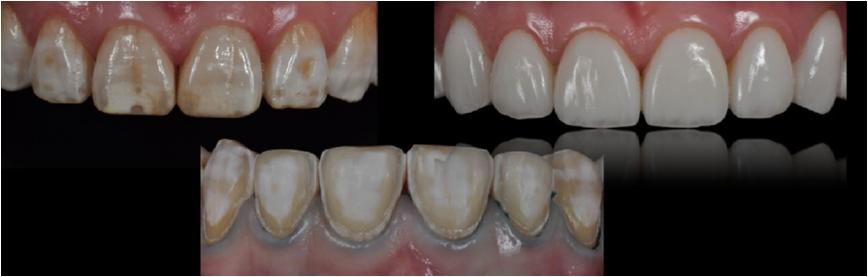

三、口腔修复:开展全瓷牙、烤瓷牙、瓷贴面、嵌体、桩核冠修复治疗、种植牙、局部活动义齿、全口义齿、咬合重建、精密附着体等修复技术,使我院义齿的功能性、美容性修复工作取得了满意的临床效果。精密附着体修复技术、种植牙技术的开展,满足了不同层次的口腔医疗需求,使修复治疗工作提到一个新层次。

贴面修复前后对比